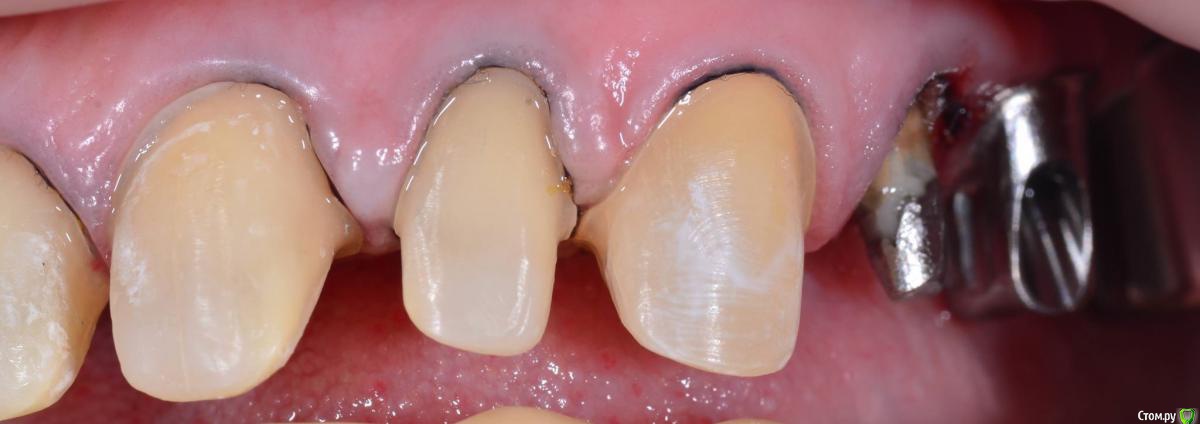

togrul Опубликовано 4 апреля, 2016 Поделиться Опубликовано 4 апреля, 2016 Добрый вечер коллеги. Восстановили зубы безметалловыми коронками Емах зубы и Циркон наслоением на имплантатах. 9 Ссылка на комментарий

chervoncevdaniil Опубликовано 5 апреля, 2016 Поделиться Опубликовано 5 апреля, 2016 Обсуждали с пациентом что цвет шеек будет отличаться от блич коронок?Не был против? Ссылка на комментарий

togrul Опубликовано 5 апреля, 2016 Автор Поделиться Опубликовано 5 апреля, 2016 Конечно . Оставил для хорошей гигиены. Так как от хирургии отказалась. Ссылка на комментарий

AndyAndy Опубликовано 5 апреля, 2016 Поделиться Опубликовано 5 апреля, 2016 Такое ощущение, судя по фото, что абатменты полированные. Техник не проводит пескоструйную обработку супрагингивальной части абатмента? Ссылка на комментарий

togrul Опубликовано 5 апреля, 2016 Автор Поделиться Опубликовано 5 апреля, 2016 Такое ощущение, судя по фото, что абатменты полированные. Техник не проводит пескоструйную обработку супрагингивальной части абатмента?Да абатменты такие пришли с фрезерного центра. Проблем небыло с фиксацией. Ссылка на комментарий